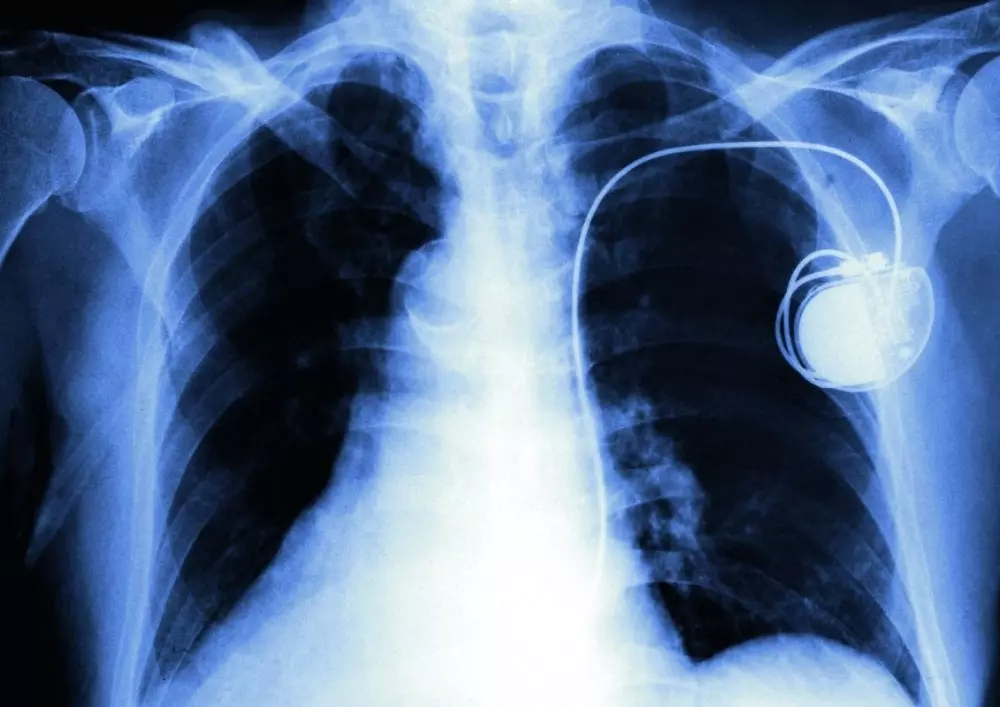

Zespół górnego otworu klatki piersiowej

Zachęcamy także do lektury artykułu, w którym opisujemy zespół górnego otworu klatki piersiowej. Autor wskazuje na liczne metody rehabilitacji w tym przypadku, co wynika z różnorodnego obrazu klinicznego grupy pacjentów oraz braku jasno określonych wytycznych klinicznych.